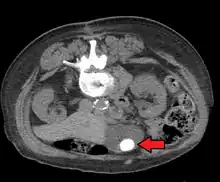

Large gallstone as seen on CT -